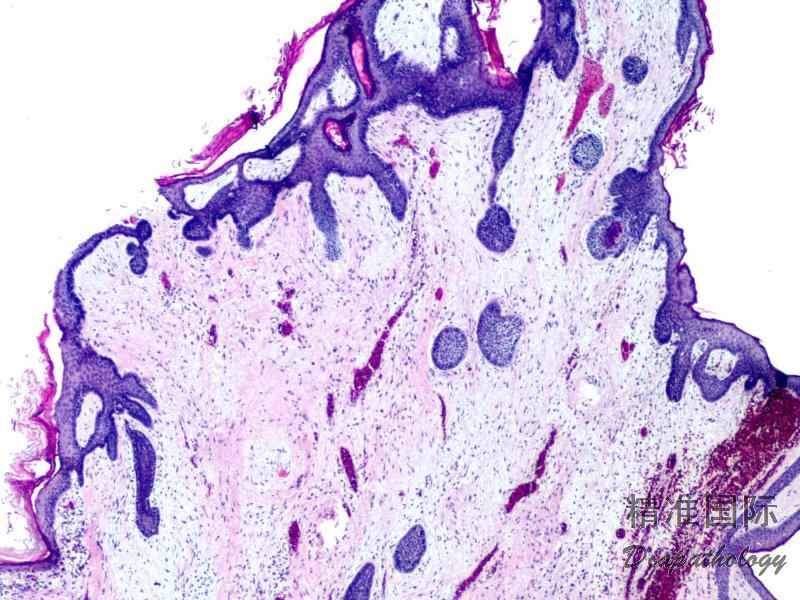

- 组织学上边界清楚,呈叶状、细胞稀疏性病变伴显著黏液样基质,温和短梭状至星状细胞伴泡状胞核,薄壁状血管,核分裂罕见,常见炎细胞浸润(尤其中性粒细胞的存在可帮助其与其他黏液病变鉴别)。皮肤黏液瘤中常见囊状扩张的毛囊结构。组织学形态类似于其他部位的黏液瘤。